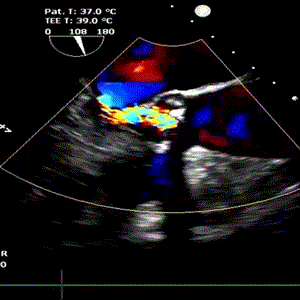

术前心脏彩超                               术后心脏彩超

术后经食道超声